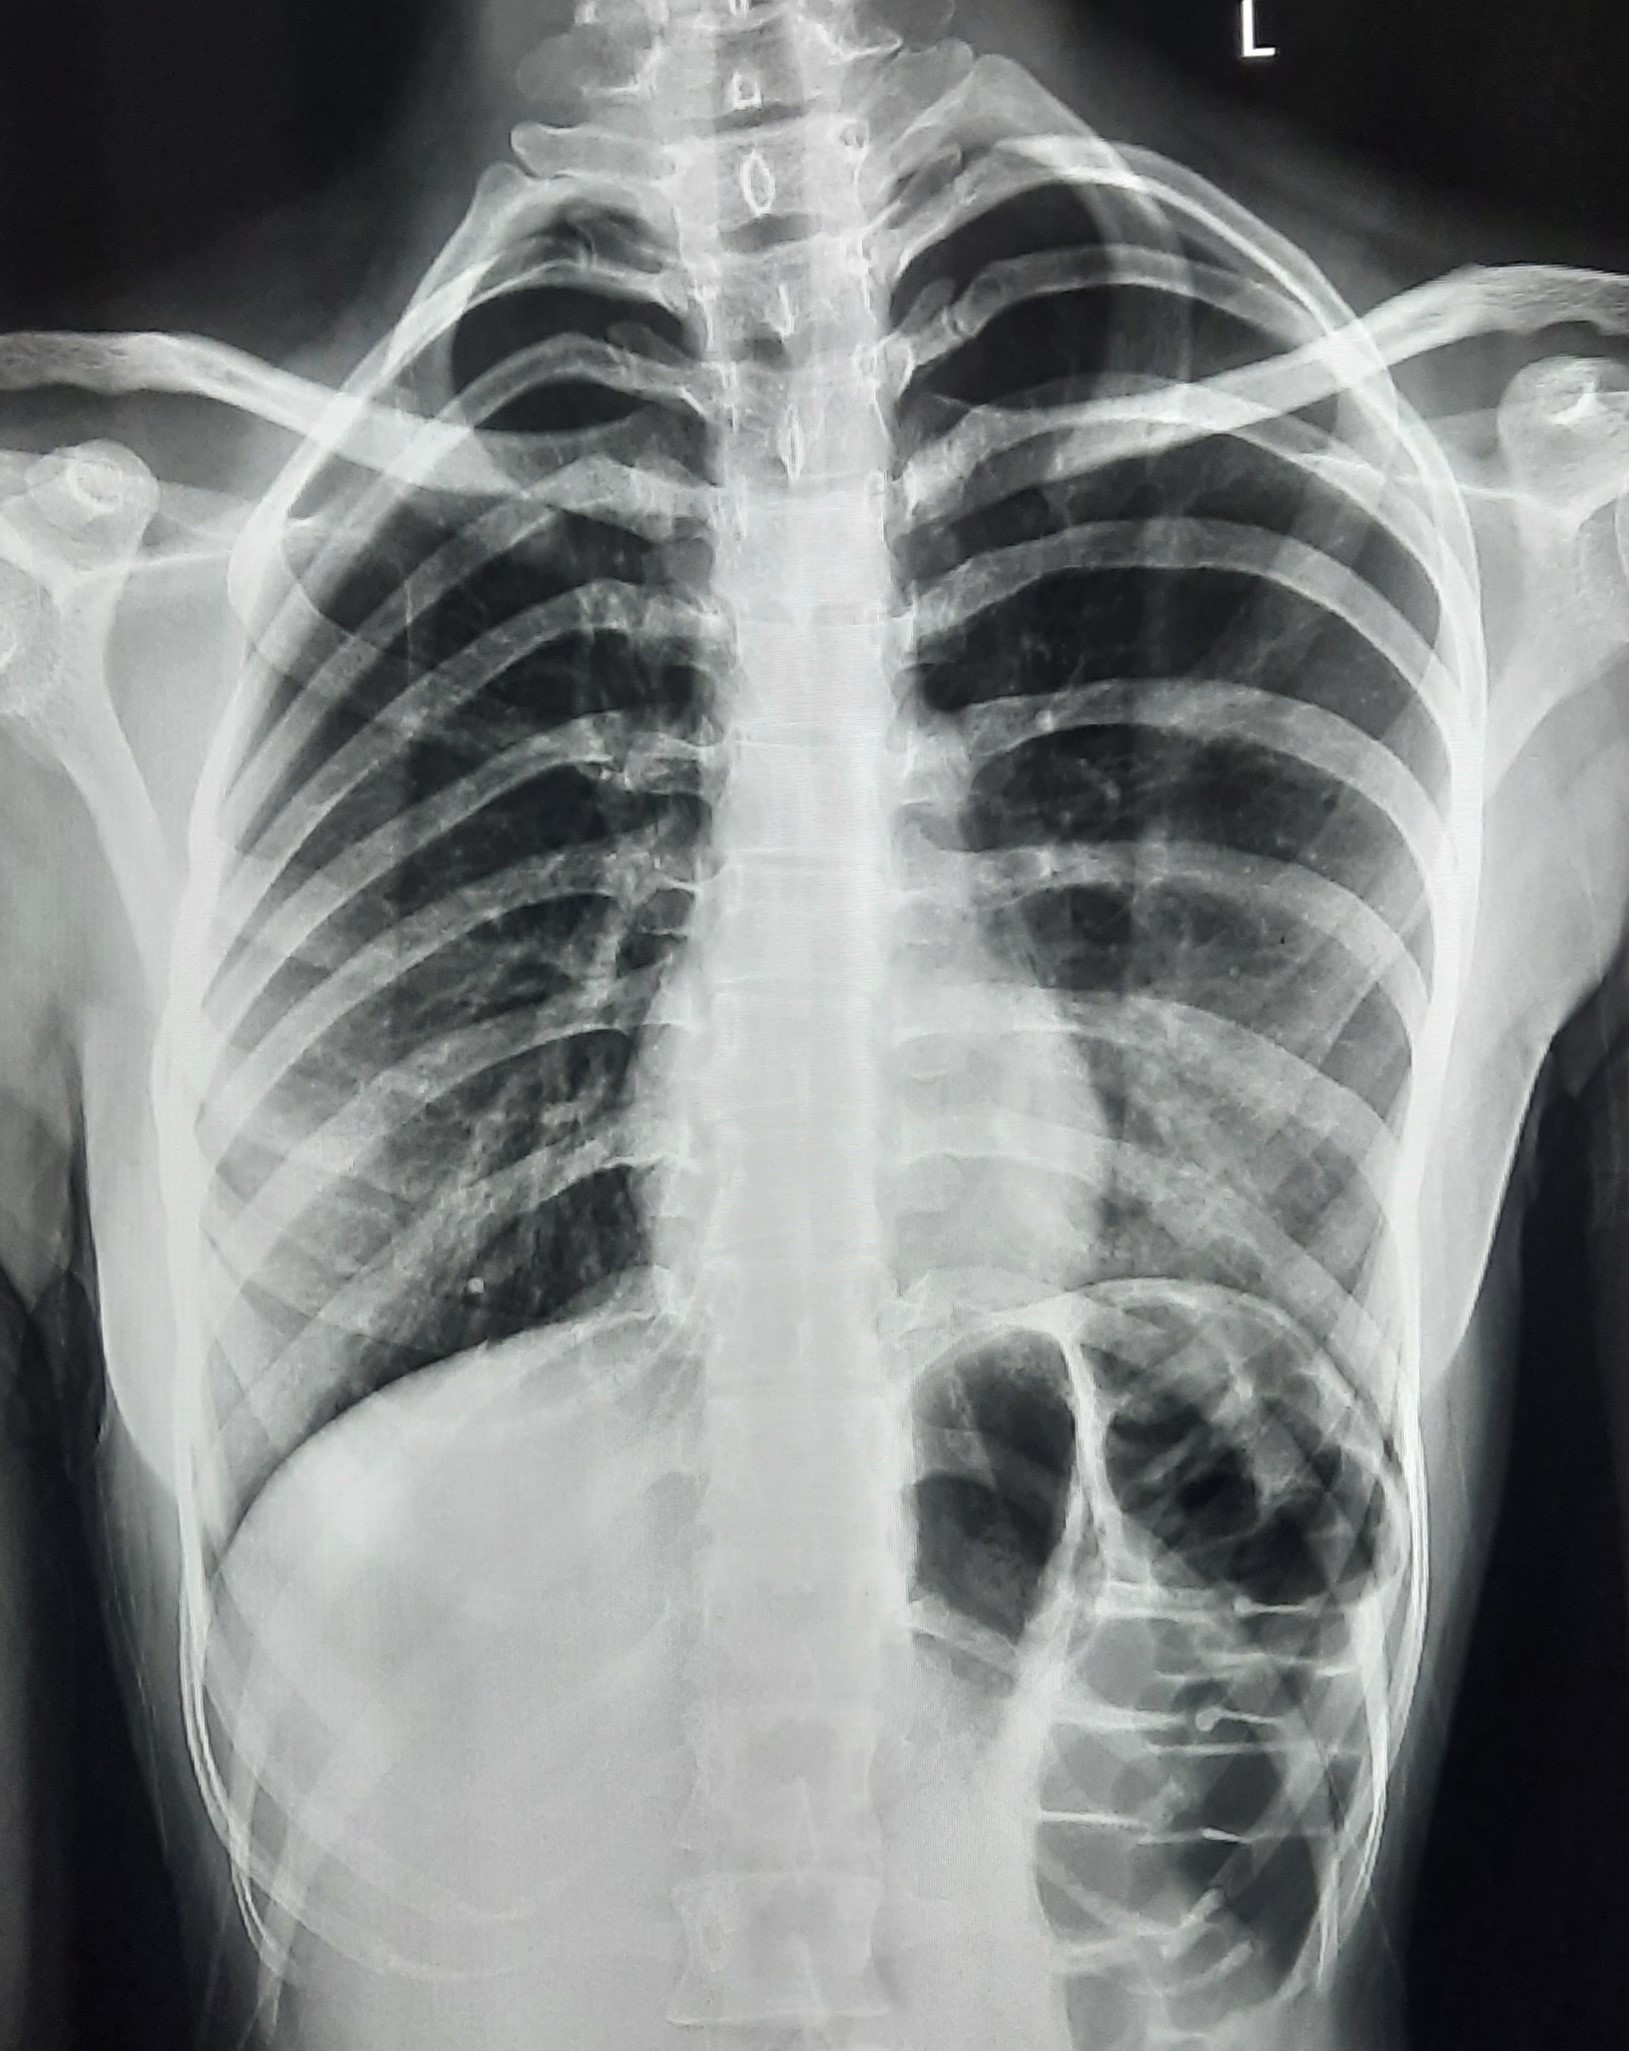

| 52 | IGGMC, Nagpur, Nagpur | P2 | 29-4420 | Hamida Bano | Consent taken on Paper | 56 Yrs. |

Provisional Diag : Post TB Sequelae With Reactivation?

Final Diag : Post TB Sequelae |

Post TB Sequelae | Tracheal Pull Left Side, Left Mid Zone & Upper Zone Fibro cavitary Lesion Present, Compensatory Right lung Hyper Infiltration Present, Few ill-defined Bilateral Lung Opacity Presnt | Abnormality visible on x-ray |